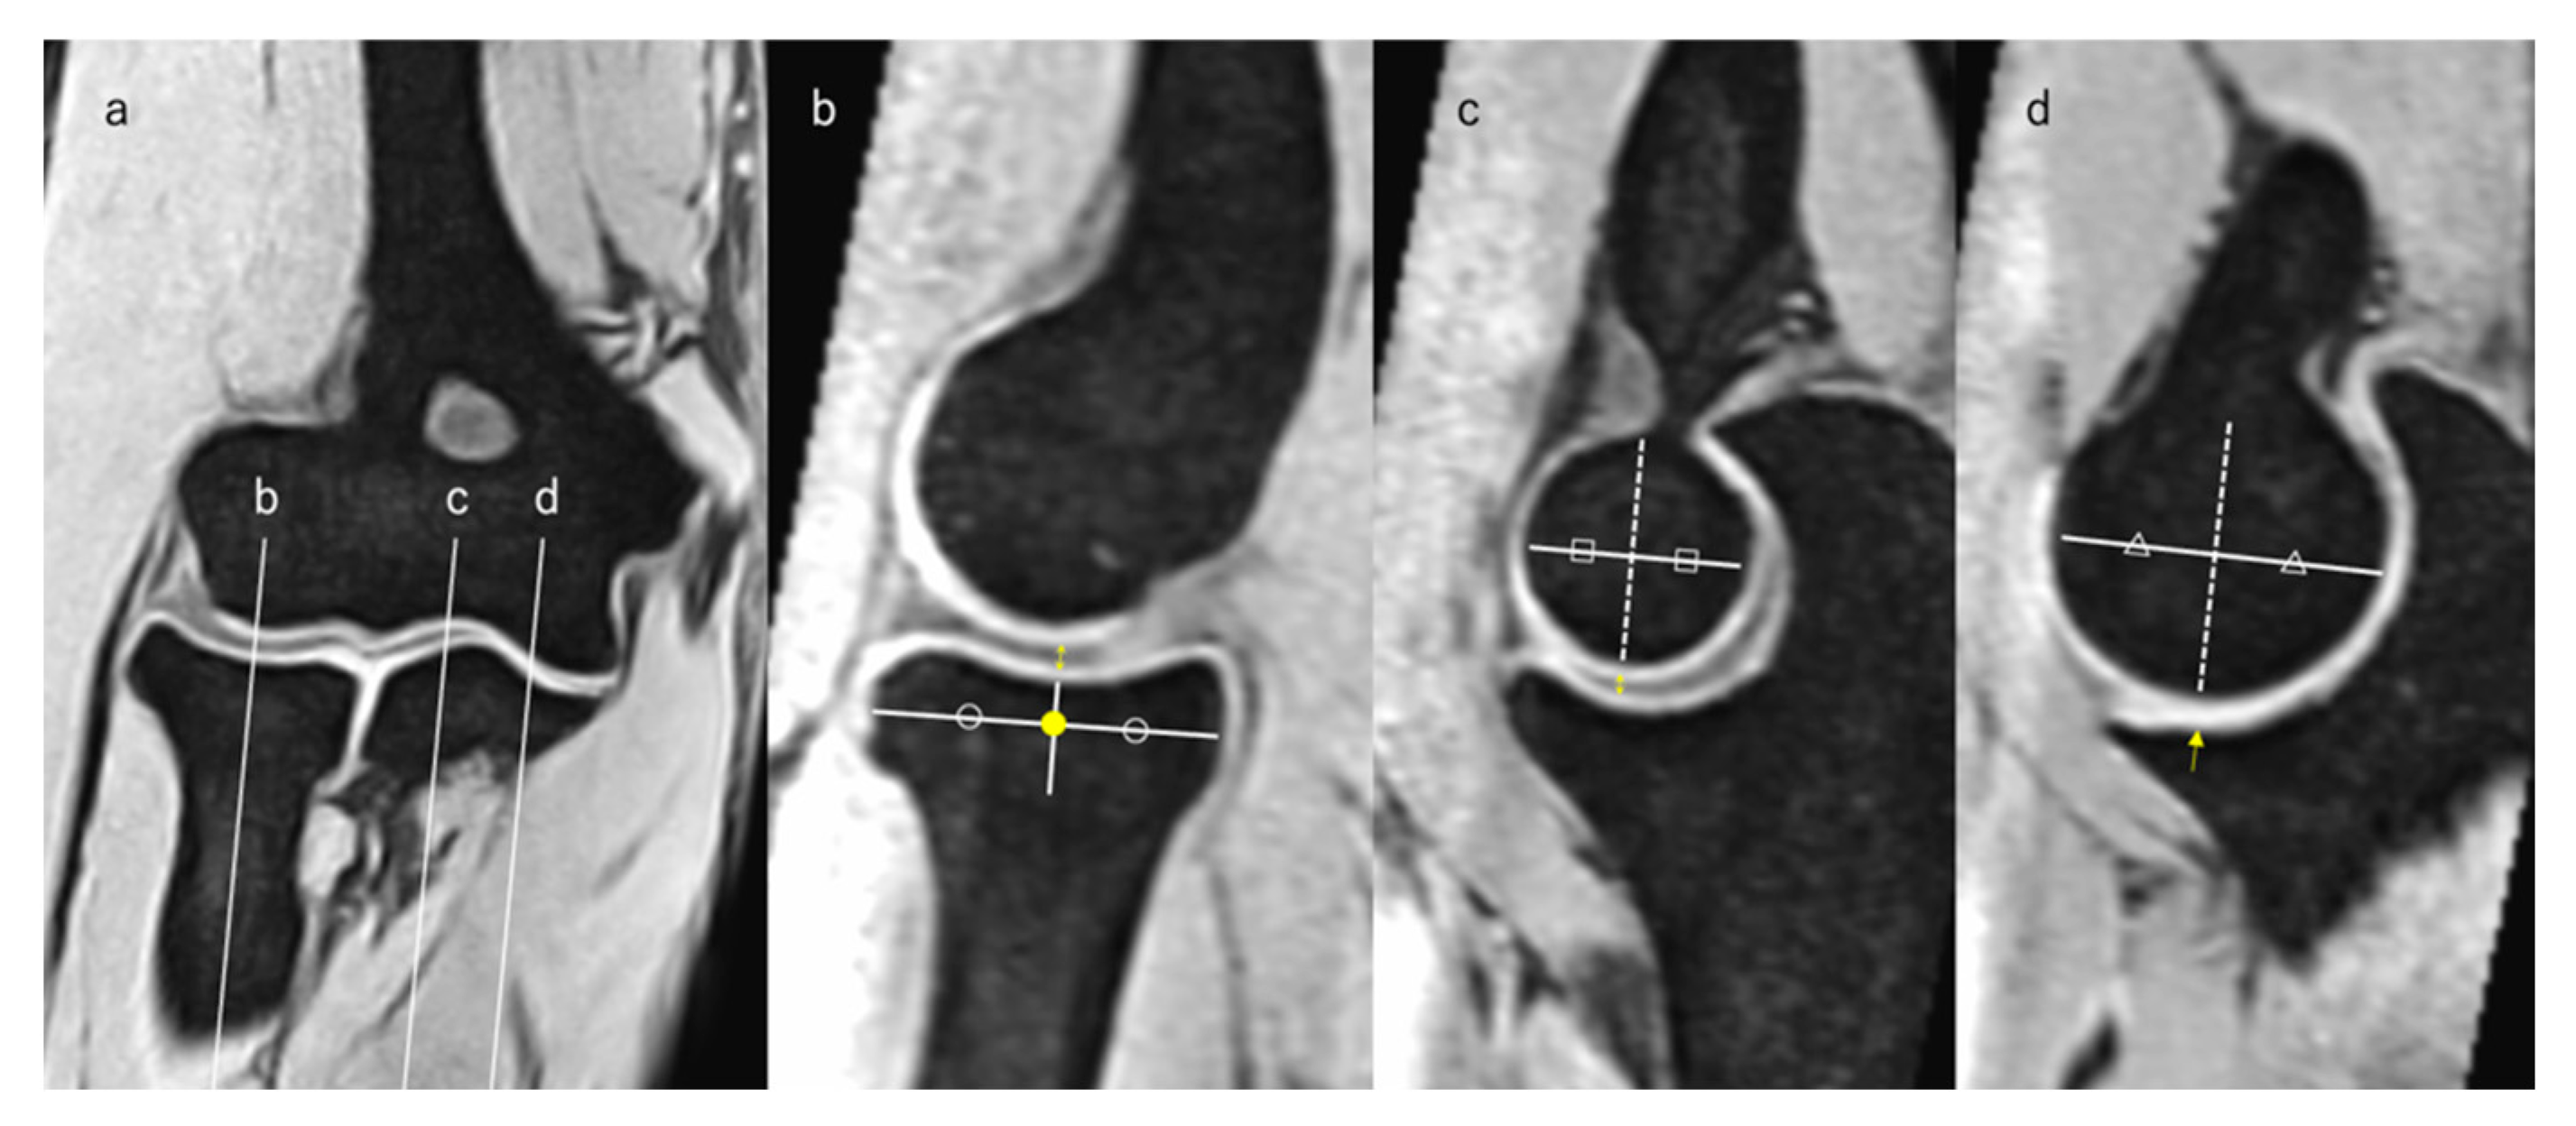

2.5. Measurement of JSW

2.6. Assessment of HACOV